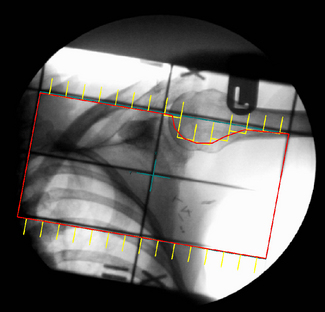

The automatic registration of the BEV and DRR have provided powerful tools to enable the planner to achieve on the TPS what was available on the simulator but with the added benefits of CT visualization (see figure 9.5A). However, for practical use, the speed of DRR calculation would have to be sub-second to give the planner ‘the feel of a simulator’.

image image

Figure 9.5 (A) Beams Eye View (BEV) on a Treatment Planning System with Digitally Reconstructed Radiograph (DRR) on Virtual Simulator; (B) Screen shot of Virtual Simulator with surface rendering and transverse slice.